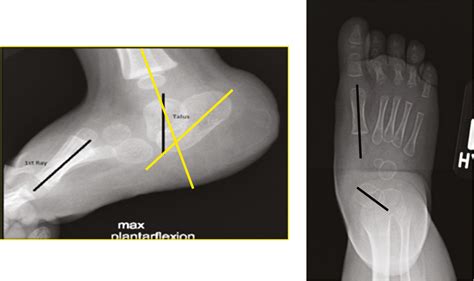

The term Rocker Bottom Feet, or congenital vertical talus in medical terminology, refers to a foot deformity where the talus bone (the main bone in the ankle joint) is locked in a fixed position. Because the bone is pushed into an abnormal angle, the foot cannot flatten or bend normally. Instead of a natural arch, the middle part of the foot curves downward, touching the ground when the individual stands.

• X-ray Imaging: This is the gold standard for diagnosis. Lateral (side-view) X-rays are typically used to measure the alignment of the talus and calcaneus bones.